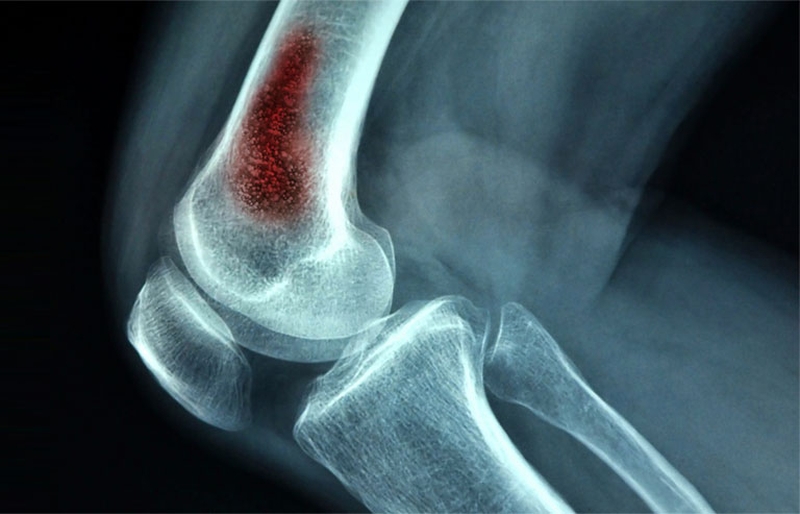

Bất cứ vị trí nào trên cơ thể cũng có nguy cơ mắc u xương ác tính, nhưng phổ biến nhất vẫn là những đốt xương dài khu vực cánh tay và chân, vòng quanh đầu gối và hai vai. Những khu vực như xương chậu, xương hàm hoặc xương sườn ít khi mắc phải các dạng u ác tính. Ngoài ra ở các đốt xương ngón tay hay ngón chân thường gặp phải dạng u xương lành tính hơn so với u ác tính.

/https://cms-prod.s3-sgn09.fptcloud.com/dau_hieu_sarcoma_xuong_u_xuong_ac_tinh_o_tre_em_va_thanh_thieu_nien_3_c94c906d3d.jpg) Hình ảnh chụp X-quang viêm tủy xương cấp

Hình ảnh chụp X-quang viêm tủy xương cấp Phần lớn, những bệnh nhân Sarcoma xương đều cần thực hiện phẫu thuật bảo tồn (Limb – Sparing). Bằng phương pháp này, bác sĩ sẽ dễ dàng loại bỏ đi khối u ác tính, cùng những vùng xương đã bị khối u xâm lớn. Với những trường hợp u xương ác tính thể nặng hoặc đã di căn đến các cơ quan khác, bệnh nhân bắt buộc phải cắt bỏ toàn bộ phần khớp gối, sau đó, thay thế bằng xương kim loại nhân tạo.